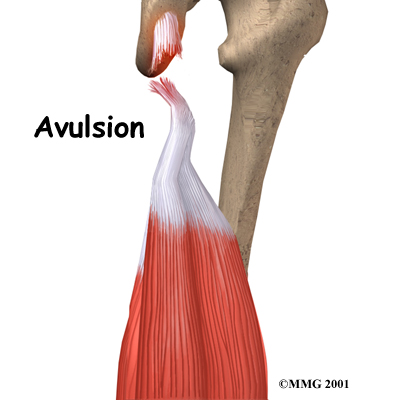

In rare cases, an injury can cause the muscle and tendons to tear away from the bone. This happens most often where the hamstring tendons attach to the ischial tuberosity. These tears, called avulsions, sometimes require surgery.

Water skiing, dancing, weight lifting, and ice skating also cause frequent hamstring injuries. These sports are also more likely to cause avulsions.

The hamstring may be pulled, partially torn, or completely torn. The injury can happen at the musculotendinous junction (mentioned earlier), within the muscle, or where the tendon connects on the ischial tuberosity (avulsion). In the rare case of a complete tear, the pain is excruciating. The torn tissues may form a hard bunch in the back of the thigh when the leg is bent. The skin may also bruise, turning purple from bleeding under the skin. This is not necessarily dangerous but can look somewhat alarming.

Surgery is rarely needed for hamstring injuries. However, it may be needed for an avulsion to reattach the torn hamstring tendon to the pelvis. If surgery is delayed after an avulsion, the tendon may begin to retract further down the leg, and scar tissue may form around the torn end of the tendon. Both of these factors make it more difficult to do the surgery.

To begin the operation, an incision is made in the skin over the spot where the hamstring tendon normally attaches to the pelvis. The surgeon locates the torn end of the hamstring tendon. Forceps are inserted into the incision to grasp the free end of the torn hamstring tendon. The surgeon pulls on the forceps to get the end of the hamstring back to its normal attachment. The surgeon cuts away scar tissue from the free end of the hamstring tendon.

The original attachment on the pelvis, the ischial tuberosity, is prepared. An instrument called a burr is used to shave off the surface of the tuberosity. Large sutures or staples are used to reattach the end of the hamstring tendon to the pelvis.